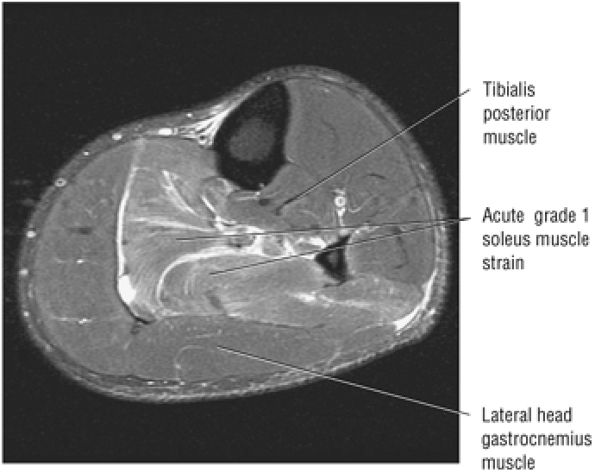

FIGURE 5.128 ● Grade 1 soleus muscle strain secondary to an Achilles rupture. Axial FS PD FSE image.